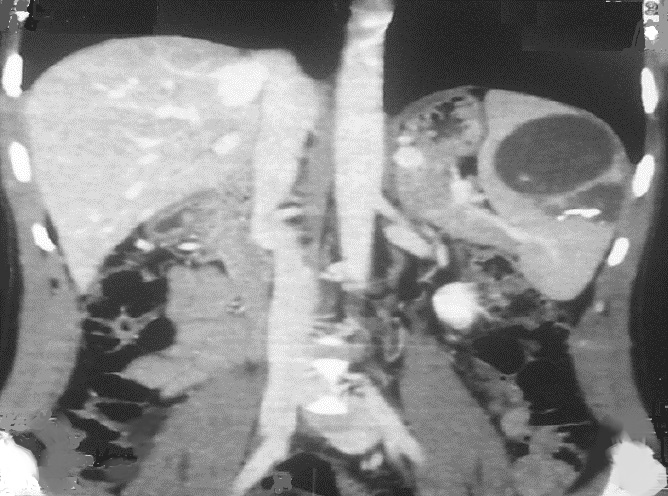

Image radiologique TDM + contrast

intraveineuyse d'un kyste hydatique multiple de la

rate . Aspect radiologique TDM est des kystes

ovalaire hy podensite a bord fine et nette , lisse

situe dans la parenchyme de la rate en forme de

rosette avec de vesicule de fille endocavitaire .

C'est la kyste hydatide de type 2 actif ( CE2) selon

la classification 2001 de OMS |

|

Même cas en coupe coronale .

Les kyste sur cette coupe etre en vue très nette et

n,a pas de rehausse apres injection de contrast

intraveineuse . Image radiologique TDM plus + C+ en

coupe coronal . L'exament serologique specifique d'

echynoccocus se verifier la diagnoctic |